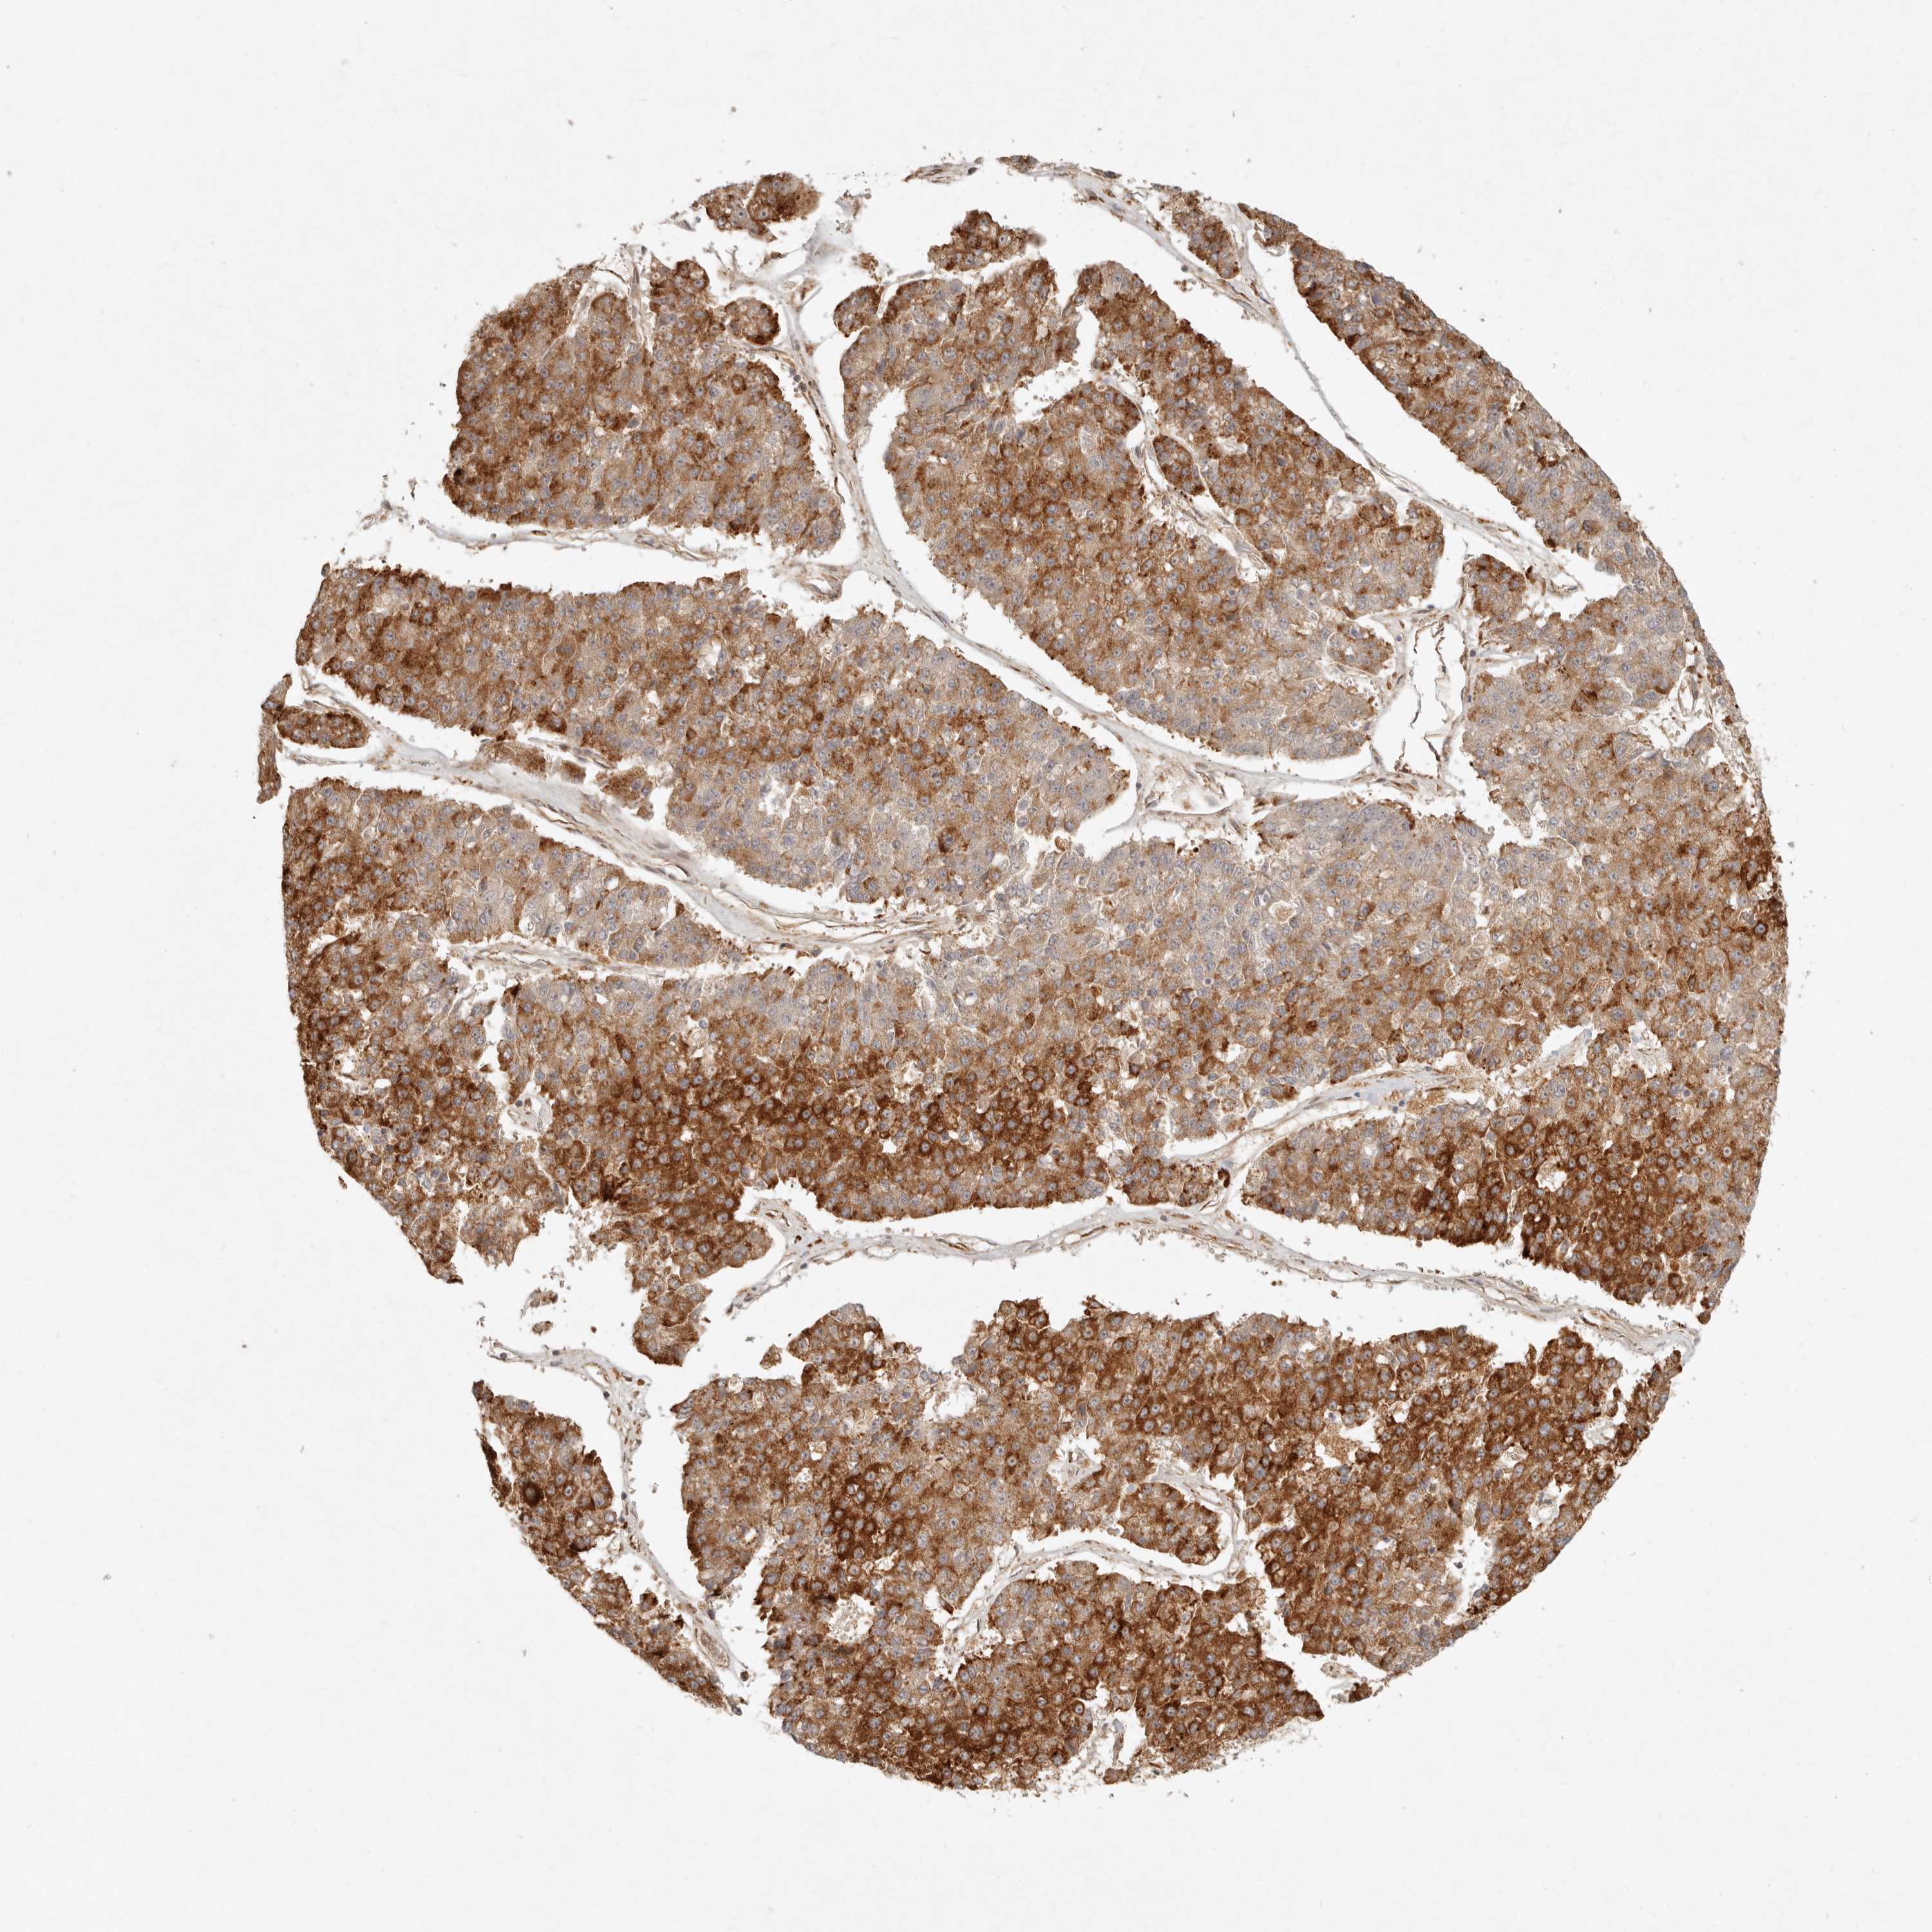

PANCREATIC CANCER - Protein expressioni

A mouse-over function shows sample information and annotation data. Click on an image to view it in a full screen mode. Samples can be filtered based on level of antibody staining by selecting one or several of the following categories: high, medium, low and not detected. The assay and annotation is described here.

Note that samples used for immunohistochemistry by the Human Protein Atlas do not correspond to samples in the TCGA dataset.

Antibody stainingi

Antibody staining in the annotated cell types in the current human tissue is reported as not detected, low, medium, or high, based on conventional immunohistochemistry profiling in selected tissues. This score is based on the combination of the staining intensity and fraction of stained cells.

Each image is clickable and will lead to virtual microscopy that enables deeper exploration of all samples and also displays staining intensity scores, fraction scores and subcellular localization as well as patient and tissue information for each sample.

Antibody HPA024770

Antibody HPA027115

Staining

High

Medium

Low

Not detected

Intensity

Strong

Moderate

Weak

Negative

Quantity

>75%

75%-25%

<25%

None

Location

Nuclear

Cytoplasmic/membranous

Cytoplasmic/membranous,nuclear

Adenocarcinoma, NOS